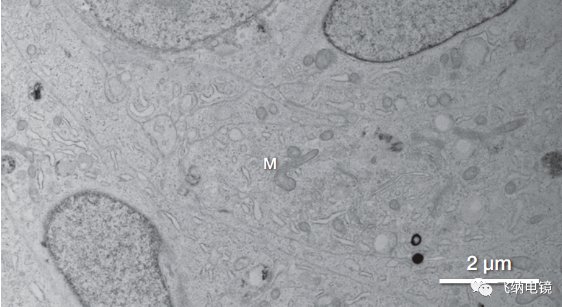

3 人类脑肿瘤组 STEM 图。图中清晰显示了细胞的超微结构特征,髓鞘轴突、线粒体和嵴结构(M)、包含细胞间质纤维和囊泡的星形细胞结构(红色箭头处)。图中可以清晰观测到细胞结构和细胞器之间的关系、/p>